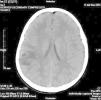

En urgencias se realiza analítica sanguínea (hemograma, bioquímica, ionograma, equilibrio ácido-base y coagulación) que resulta normal; y una TC craneal sin contraste en la que se observa una lesión nodular hipodensa de aspecto quístico con un elemento nodulillar mural sólido, de localización parietotemporal derecha con edema vasogénico asociado (fig. 1). Además se evidencian dos lesiones nodulares hipodensas, probablemente quísticas, con calcio puntiforme mural, localizadas a nivel frontal parasagital izquierdo y parietal derecho, sin edema asociado (fig. 2).

Figura 1.TC craneal. Lesión nodular hipodensa parietotemporal derecha.